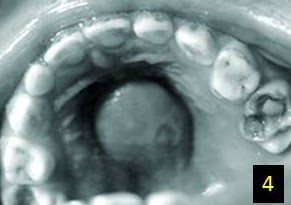

Μία ανάλογη περίπτωση οδοντογενούς υπερώιου αποστήματος με κατάληψη της μεσότητας της υπερώας εντοπίσαμε στη βιβλιογραφία(Εικ. 4). Αφορούσε ένα 5-χρονο κορίτσι και οφειλόταν στον άνω δεξιό δεύτερο νεογιλό γομφίο, μετά από την εξαγωγή του οποίου, η βλάβη αποκαταστάθηκε.

Εικ. 4: Απόστημα στη μεσότητα της υπερώας από τον #55